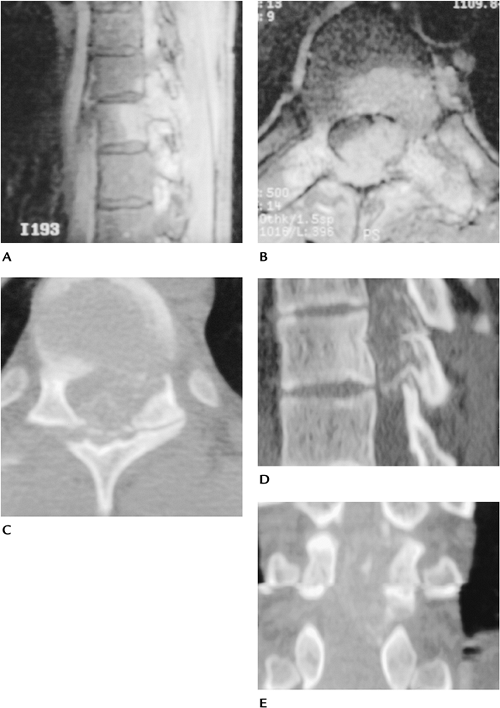

FIGURE 10-10 Osteoblastoma. Sagittal (A) and axial (B)

contrast-enhanced T1-weighted images showing a large enhancing lesion that appears to involve the body and neural arch with spinal cord compression. Axial (C), sagittal (D), and coronal (E) CT images demonstrate matrix calcification or ossification with a thin cortical rim characteristic of osteoblastoma. |